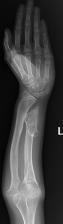

桡骨陈旧性骨折骨不连、畸形

尺骨短缩畸形并软骨瘤 桡骨小头脱位